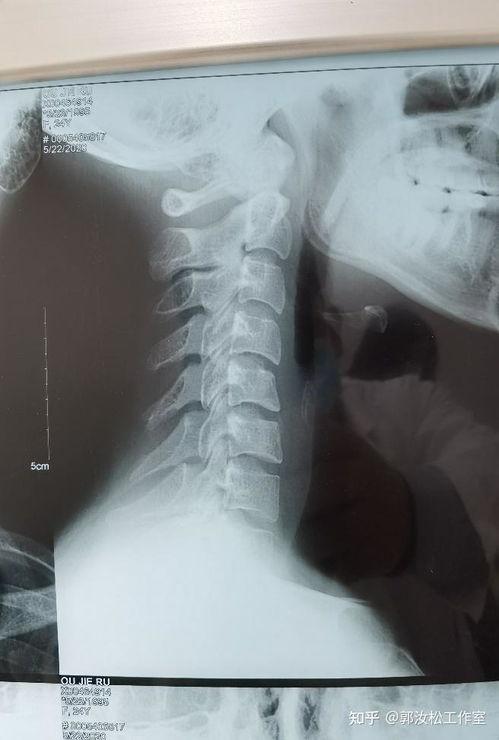

刘焰刚颈椎扳法,顾名思义,就是通过特定的手法来调整颈椎,缓解颈椎病带来的痛苦。这个方法源自我国传统中医,经过刘焰刚老师多年的研究和实践,已经形成了一套完整的治疗体系。

三、刘焰刚颈椎扳法的效果如何?

那么,刘焰刚颈椎扳法的效果究竟如何呢?据网友分享,这个方法确实有一定的疗效。以下是一些真实案例: